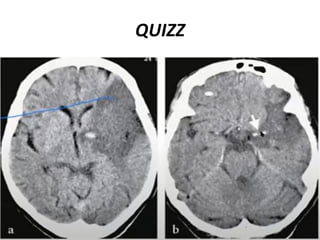

QUIZE !!!

QUIZZ